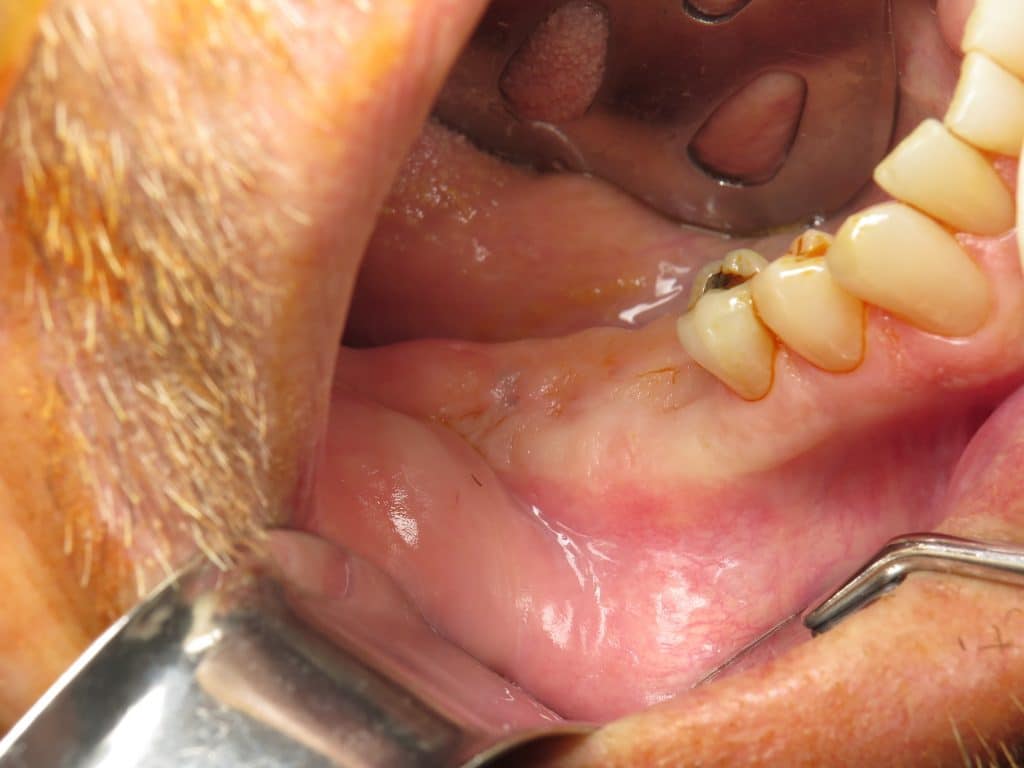

Abstract aims this review aimed at investigating the effect of membrane exposure on guided bone regeneration. This procedure is done in preparation for dental implants. the effect of membrane exposure on guided bone regeneration. based on the findings of this study, membrane exposure after gbr procedures has a significant detrimental influence on.

Exposed Membrane Bone Graft the effect of membrane exposure on guided bone regeneration. Abstract aims this review aimed at investigating the effect of membrane exposure on guided bone regeneration. This procedure is done in preparation for dental implants. the effect of membrane exposure on guided bone regeneration. based on the findings of this study, membrane exposure after gbr procedures has a significant detrimental influence on.

Bone Graft and Membrane Procedure at America Dental Clinic Exposed Membrane Bone Graft the effect of membrane exposure on guided bone regeneration. Abstract aims this review aimed at investigating the effect of membrane exposure on guided bone regeneration. This procedure is done in preparation for dental implants. based on the findings of this study, membrane exposure after gbr procedures has a significant detrimental influence on. Exposed Membrane Bone Graft.